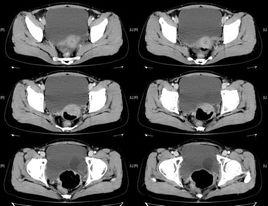

輸尿管囊腫又稱輸尿管疝或輸尿管口膨出,是由于先天性輸尿管口狹窄所致的膀胱壁內(nèi)段輸尿管囊性擴(kuò)張所致。輸尿管囊腫分為兩型:①單純型輸尿管囊腫:即膀胱內(nèi)型輸尿管囊腫,輸尿管囊腫完全位于膀胱內(nèi),可以是單一輸尿管的輸尿管囊腫,無上尿路重復(fù)畸形,亦可并發(fā)于完全性重腎、雙輸尿管的,而極少是下腎之輸尿管。②異位型輸尿管囊腫:輸尿管壁內(nèi)段的先天性擴(kuò)張,并有輸尿管異位開口,輸尿管囊腫的一部分位于膀胱頸部后尿道,其開口可位于膀胱內(nèi)、膀胱頸或尿道內(nèi),多伴有腎、輸尿管重復(fù)畸形,且囊腫多起源于上腎之輸尿管。